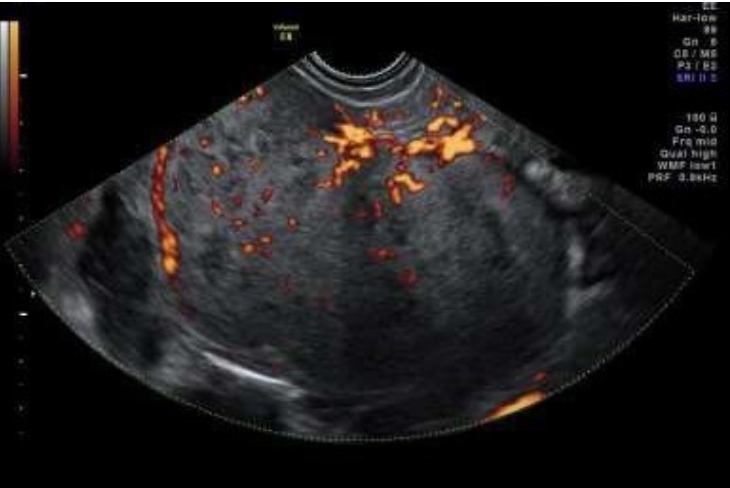

Dysgerminom är en av de vanligaste typerna av groddcellstumör och förekommer ofta hos unga kvinnor; 80 % är yngre än 30 år. Tumörformen är sällsynt hos kvinnor som genomgått menopaus. AFP- och hCG kan vara förhöjda liksom även LD. Bilaterala tumörer ses hos 10–15 % av kvinnorna. Tumörerna är solida, lobulerade, välvaskulariserade och ofta stora (10–15 cm) vid diagnos. Se bild 1.

Bild 1. Snabbväxande dysgerminom hos 22-årig gravid kvinna med förhöjt S-LD.